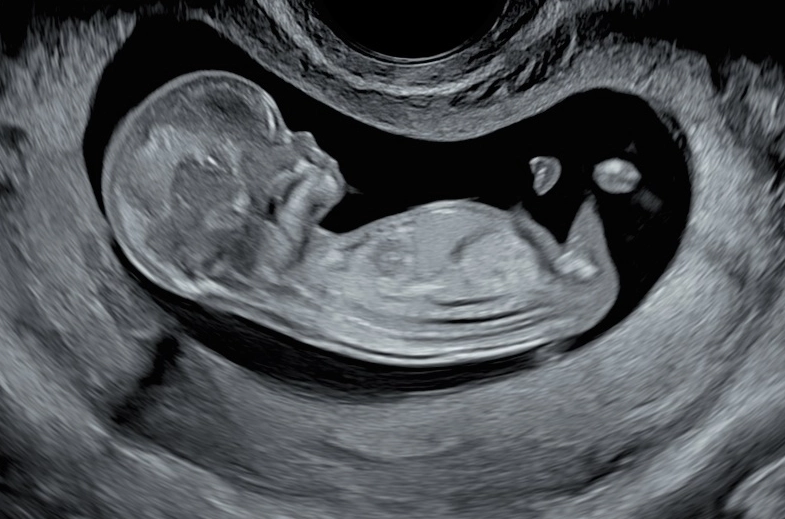

2. Ultrasound Scans

Ultrasounds track physical development. Key markers include:

- Crown-rump length (early pregnancy)

- Head circumference and abdominal circumference

- Femur length

- Presence of all major organs

- Amniotic fluid levels

Ultrasounds are the primary tool. They measure key parameters: